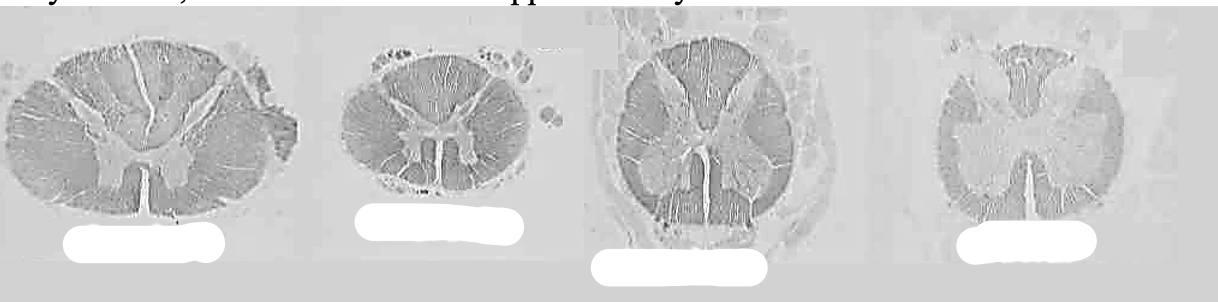

What level does the spinal cord end in adults

L2

How to tell apart different levels of the spinal cord

Which part of the spinal cord recieves sensory fibers and which part recieves motor fibers?

Dorsal root= sensory fibers

Ventral root= motor fibers

What is the name of the hole in the middle of the spinal cord and what does it contain?

The spinal canal; contains the spinal cord

Identify different sections of the spinal cord

Label